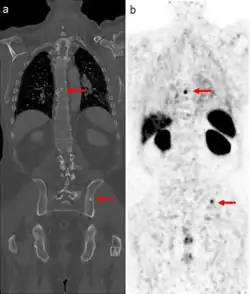

CT scan (left) and gallium PSMA PET scan (right) of patient with prostate cancer metastases in the bones

The positron emitting isotope, 68Ga, can be used to target prostate-specific membrane antigen (PSMA), a protein which is present in prostate cancer cells. The technique has been shown to improve detection of metastatic disease compared to MRI or CT scans.[25]